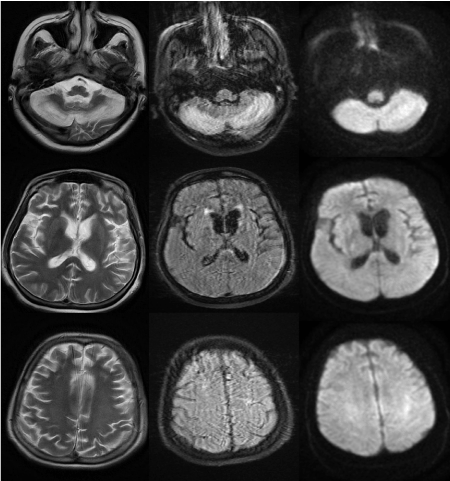

Figure 2. T2w,T2 sagittal, T2 flair brain imaging; Edema and thickening due to involvement in cortical gray matter areas of cerebellum,basal ganglia,frontal and parietal lobe.Diffusion images in the same regions of diffusion restriction